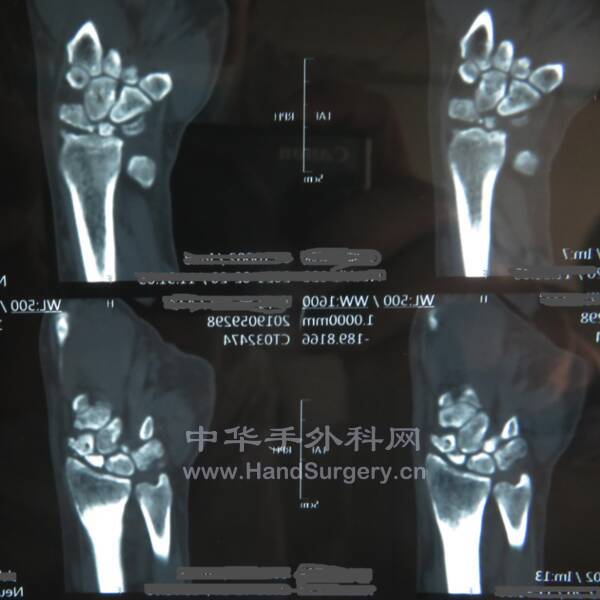

本帖最后由 zhangwenlong 于 2021-2-21 21:24 编辑

SLAC或SNAC腕手术治疗方式:

1、舟骨切除,四角融合术

2、近排腕骨切除术

3、头月融合,舟骨三角骨切除术